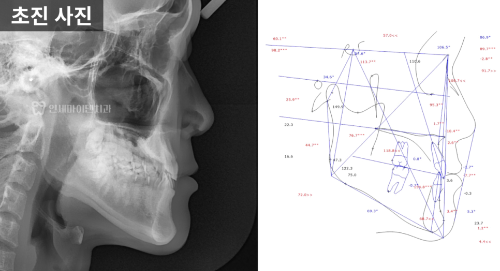

3급 부정교합 진단

방사선 사진을 분석해 보니

위턱보다 아래턱이 발달한 3급 부정교합,

흔히 '주걱턱'이라고 하는 상태였습니다.

아래 앞니의 각도가

정상치보다 훨씬 작은 68.7도로

안쪽으로 쓰러져 있었습니다.

정면 방사선에서는

위턱과 아래턱의 폭 차이가 정상보다 훨씬 커서

위턱이 약 10mm 이상 좁은 상태가 확인됐습니다.